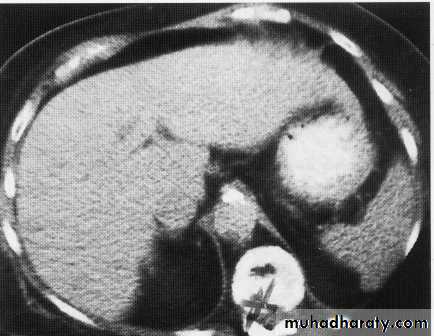

hepatic mets

hepatic mets,arterial phase

hepatic mets venous phase